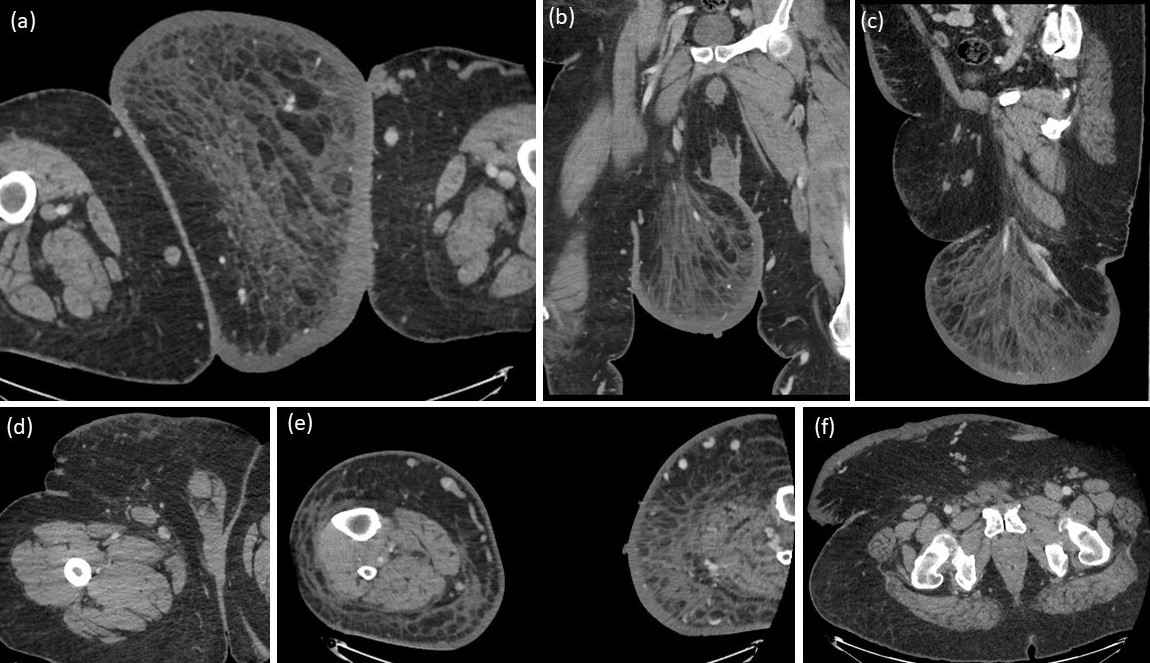

The general surgeon requested enhanced computed tomography (CT) scan (Figure 1 and Figure 2) for the patient as an initial imaging investigation to characterize the nature of the mass. It demonstrated the presence of large mass of fat attenuation in the supero-medial aspect of the right thigh. There is marked skin thickening overlying the mass, involving the anterior abdominal wall as well as bilateral lower thighs. The patient reported history of previous visit to the emergency department two years back with a complaint of left foot pain and swelling. Radiograph was performed at that time (Figure 3) and showed diffuse thickening of the heel-fat pad. Based on the features demonstrated in CT and foot radiograph, the differential diagnosis of massive localized lymphedema (MLL) or atypical lipoma lesion was given.

Radiologically, the CT and MRI appearance of the lesion resembles a large pendulous mass of adipose tissue, devoid of fascial or muscle involvement. This directly correlates with the histopathological findings of dermal fibrosis, edema, and fat partitioned by fibrous septae. Specifically, edema tracks along the fibrous septa in a lace-like pattern, accompanied by associated dermal thickening. Contrast administration reveals only mild enhancement in the dermis, consistent with the features observed in lymphedema [9-11].